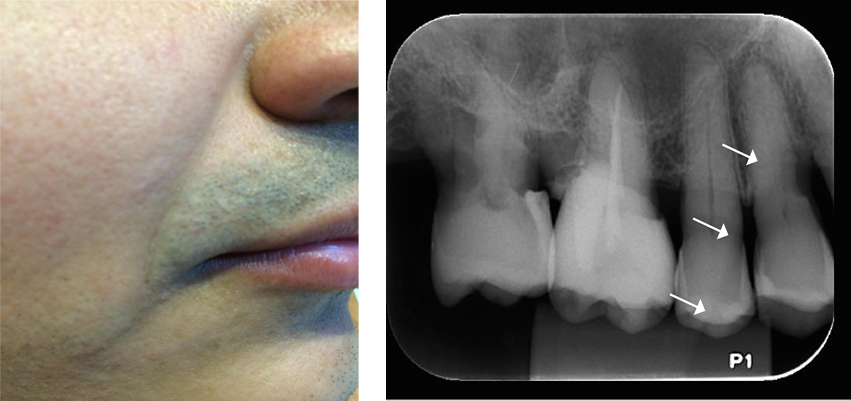

A fosseta mirtiforme corresponde à área radiolúcida difusa próxima aos ápices dos incisivos laterais, corresponde ao registro da fóvea ou depressão óssea supraincisal.

Para evitar ser confundida com uma condição patológica, deve ser observada a integridade da lâmina dura dos dentes adjacentes.

O assoalho da cavidade nasal e a parede anterior do seio maxilar são frequentemente observados radiograficamente sobrepostos, formando o Y invertido de Ennis, radiopaco na imagem.

O sulco nasolabial é um espesso tecido da bochecha sobreposto aos dentes e ao processo alveolar e torna-se mais evidente com o avanço da idade. Radiograficamente, estende-se da região do canino à região de pré-molares.